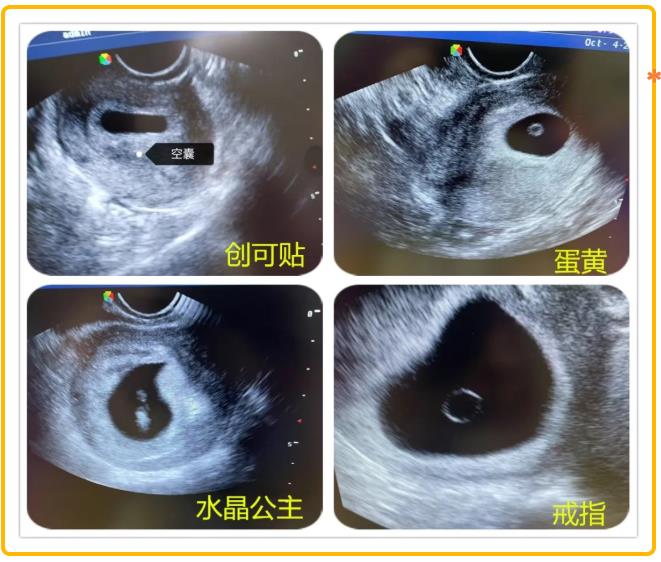

当超声探头的凝胶在腹部晕开涟漪,显示屏上的光斑便化作生命的星图。那些不足指甲盖大的孕囊,有的像春日里第一颗露珠,有的像蓝天下的云朵,还有的像时间的沙漏……“小豌豆”是六周的胚芽,绒毛膜正在形成玫瑰花瓣般的皱褶;“蒲公英”是八周的胚胎,羊膜腔里漂浮着绒毛的丝絮;“星星是意外停育的孕囊,却依然保持着完美的图形。

无影灯下,金属器械碰撞的清脆声中,总流淌着温柔的诗句。麻醉师在推注丙泊酚前会轻声念诵:“你原是银河的星子,偶然投影在春天的湖”,让患者在美妙的意象中沉入梦境。最特别的还是胚胎病理标本瓶,每个透明容器上都贴着名字:云朵、小水滴、水晶公主、沙漏、天平、创可贴……将无法言说的遗憾转化成语言的琥珀。它们用独特的存在方式告诉我们:生命是一段奇妙的旅程,每一段经历都值得我们珍惜,纵然逝去,也要留下温柔的印记。

请相信,当你为每一个孕囊轻轻唤作一个名字,它们便不再是冰冷的数据,而是有了温度的存在——那一刻,它们分外美丽,而你也不再孤单。